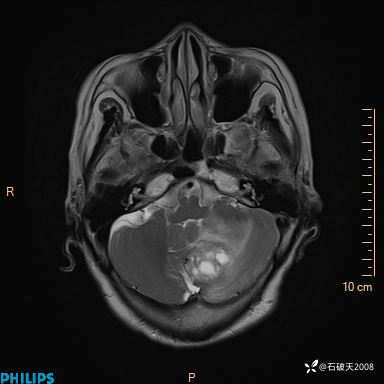

T2